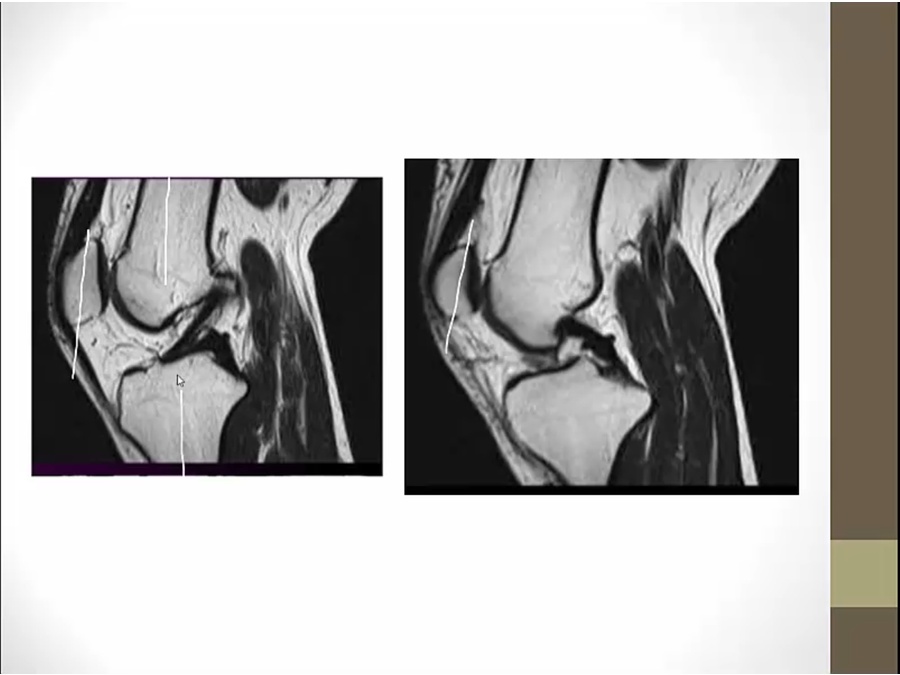

left pic: black line attaching to anterior tibia (anterior cruciating)

right pic: black line attach to posterior tibia (posterior cruciating)